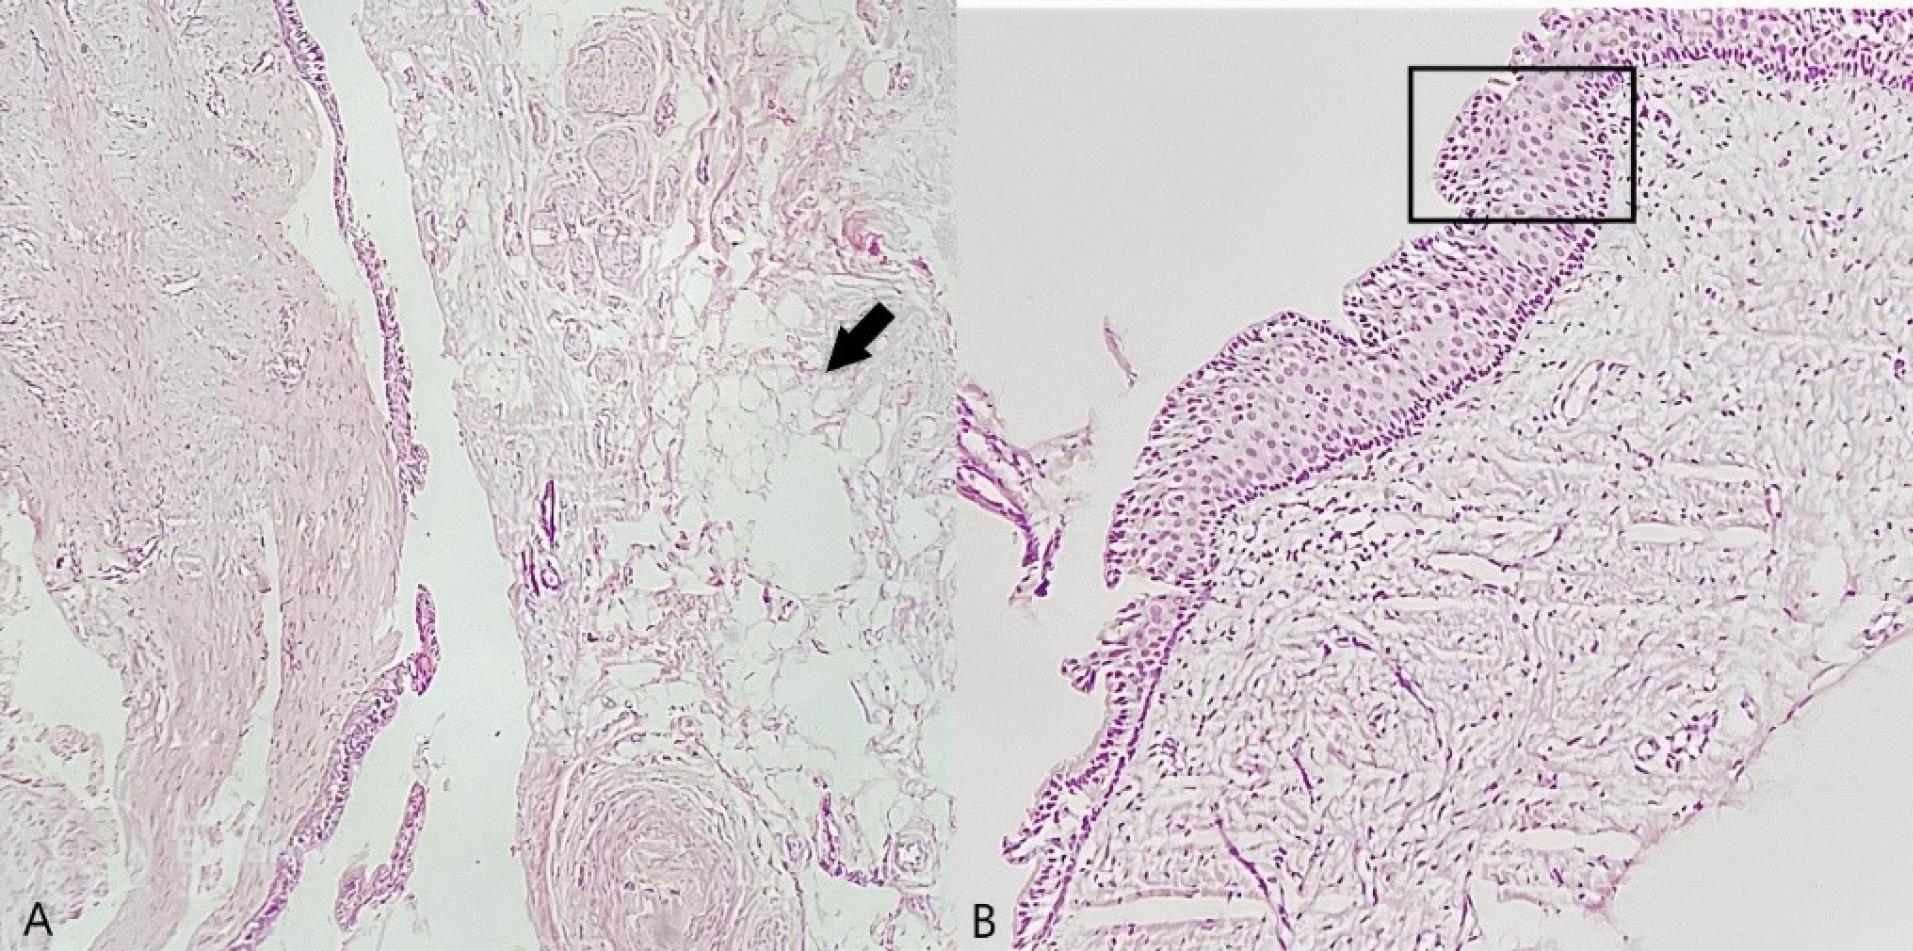

A 68-year-old man was referred to the clinic with a chief complaint of swelling in the anterior palatal portion of the maxilla for the last two months. The patient had no history of systemic problems or medication use. He also mentioned that five years ago, he had undergone full-mouth reconstruction therapy. Intraoral examination revealed a swelling in the midline of the anterior maxilla, near the area where central implants had been inserted (Figure 1). The patient reported no signs of suppuration or pain.

Figure 1.

Clinical image and panoramic view of the swelling in the anterior maxilla

A full radiographic examination was requested. Following radiographic evaluation of panoramic radiograph and sections of cone-beam computed tomography (CBCT), an oval-shaped, unilocular radiolucency with a well-defined boundary was observed that not only surrounded the apex of the right central implant but also disturbed the nasopalatine canal and nasal floor (Figures 1 and 2).